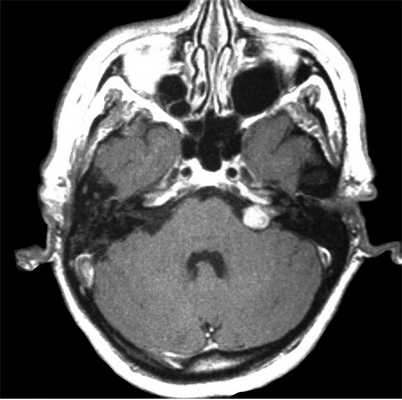

На Т2-взвешенных МРТ головного мозга невриномы имеют округлую или овальную форму, изоинтенсивны или слегка гиперинтенсивнее белого вещества, хорошо видны на фоне яркого ликвора цистерны. Крупные опухоли могут подвергаться кистозной дегенерации и включать сосуды. Мелкие невриномы имеют компонент во внутреннем слуховом проходе и как бы “утолщают“ нерв на МРТ изображениях. Как показывает опыт МРТ СПб полностью внутриканальцевые невриномы встречаются редко. МРТ в СПб при шванномах мы проводим обычно с контрастированием. Контрастирование неврином при МРТ с контрастированием хорошее, обычно однородное. Нельзя забывать, что во внутреннем слуховом проходе также может быть воспалительный процесс (неврит), приводящий к сходной клинической симптоматике. При МРТ неврит виден как отёк нерва, имеется контрастное усиление на МР томограммах.

МРТ головного мозга. Невринома слухового нерва слева с внутриканальцевым компонентом. Аксиальные Т1-зависимая МРТ, Т1-зависимая МРТ с контрастированием, и корональная Т1-зависимая МРТ с контрастированием.